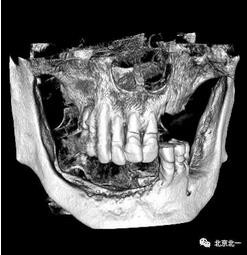

術(shù)前檢查片下頜骨季度萎縮,右側(cè)下頜下牙槽神經(jīng)管幾乎位于牙槽嵴頂。不能行常規(guī)種植。采用A04技術(shù)可實(shí)現(xiàn)即即刻種植一日戴牙夢(mèng)想。

圖一至圖六明顯看出右側(cè)頦孔位于牙槽嵴頂。很清晰看出頦孔區(qū)的U型形狀。